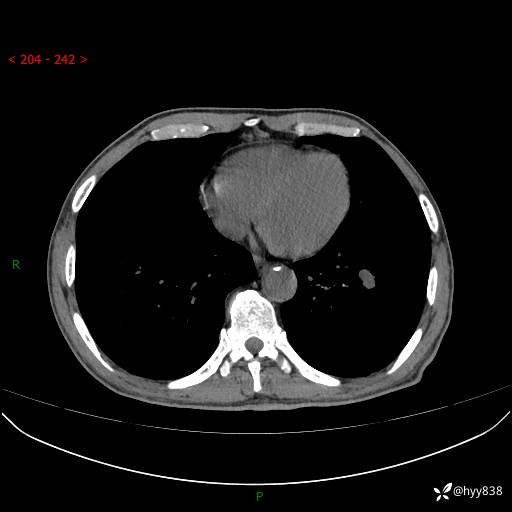

胸部CT平扫